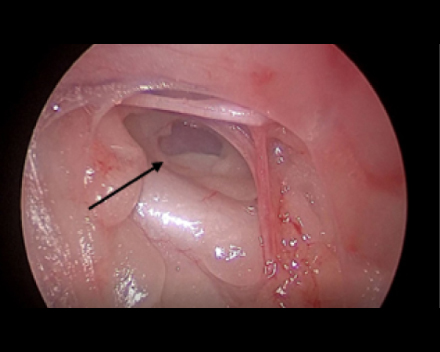

胸腔鏡で覗くと胸管がキレイに見えます(黒矢印)。

必ず、反対側の胸管も確認できるところまで剥離します。(黒矢印)